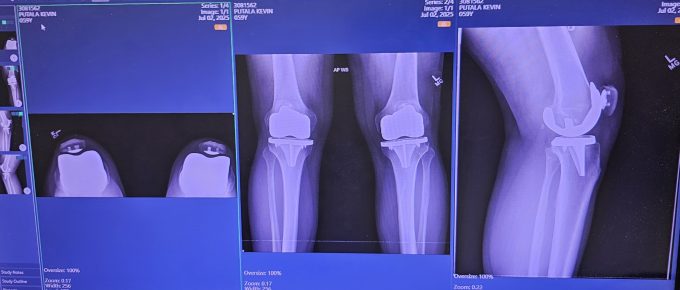

There comes a moment in every serious martial artist’s life when the body begins to speak more loudly than the ego. For some, it’s a minor injury. For others, like myself, it is something far more …